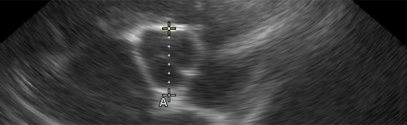

Ecografía POCUS en pequeños animales

Realice ecografías en las urgencias de la forma más adecuada. Al incorporar el POCUS como herramienta diagnóstica en nuestras urgencias, nos ayudará tanto a identificar.....

Ecografía abdominal básica en pequeños animales

El objetivo fundamental de este curso es presentar los protocolos de exploración correctos, la asimilación por parte del alumno de aquellos conceptos básicos en cuanto al.....